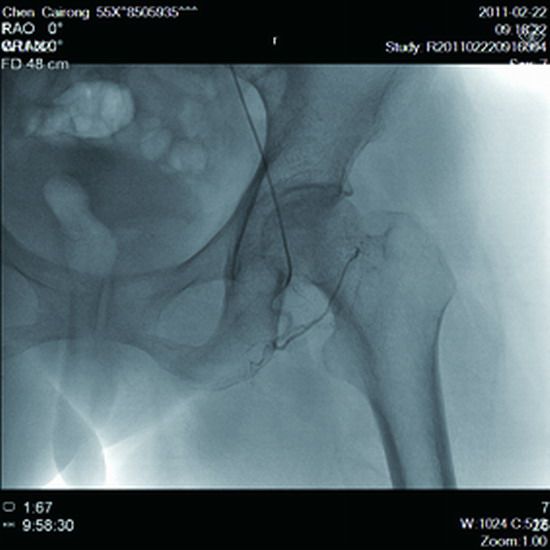

患者,女,55岁,双侧髋关节疼痛半年,下肢酸胀,行走一段路后疼痛加重,为求医来院治疗,检查结果显示双侧股骨头缺血性坏死二期,外周介入科张伯鸿主任看过病人后,经过慎重考虑,认为介入治疗可行,手术在DSA下如期进行,穿刺右侧股动脉,在导丝的指引下将微导管超选送到左侧股骨头供血动脉,造影,显示供血动脉近端狭窄,远端血管网消失(见图1),血流速度慢,将溶栓、扩血管、改善循环的药物通过注射泵直接注入到供血动脉内,再次造影显示近端血管狭窄改善,血流速度加快,远端血管网清晰可见(见图2)。再将导管成袢送入右侧旋股动脉口,将药物直接注入到供血动脉内(见图3)。患者手术后第二天,双腿疼痛即有缓解,术后五天明显缓解,术后7天出院,随访疼痛基本消失,无不良反应。